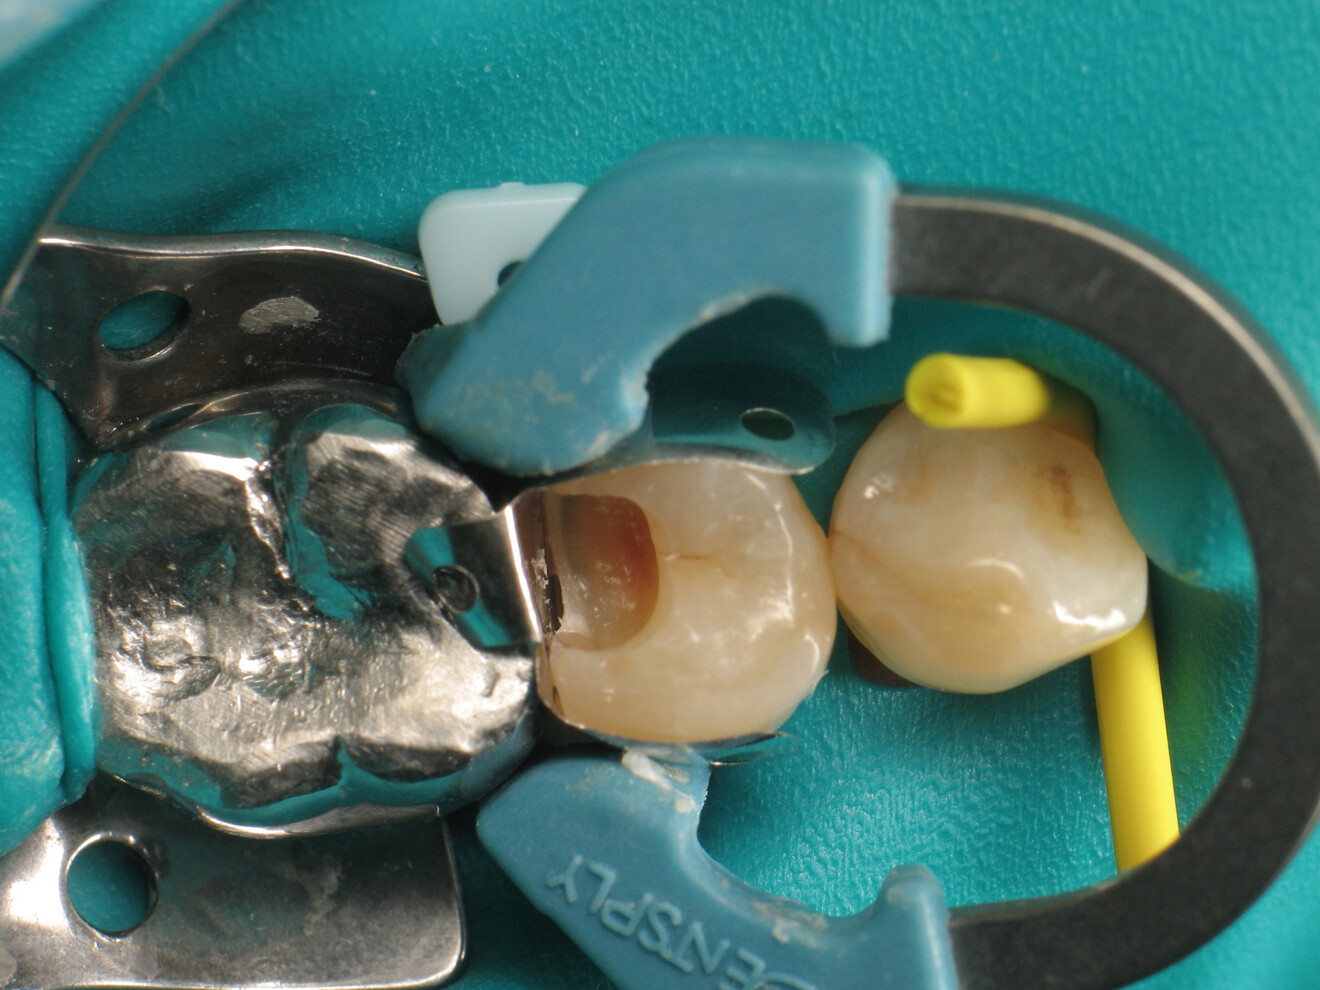

Fig. 3: Cavity after excavation.